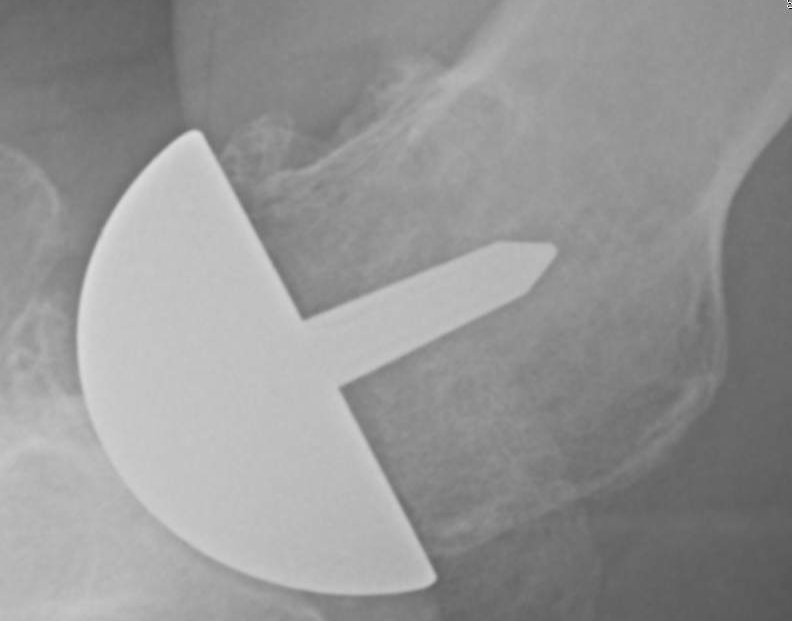

His x-rays at the time of his initial clinic visit are shown below. There is a suggestion of incomplete seating of the hemicap, lucency around the central peg, and varus positioning.

He desired revision arthroplasty. Specimens for culture were obtained before antibiotic administration. The resurfacing prosthesis was grossly loose and the bone beneath it very soft. A hemiarthroplasty was inserted using Vancomycin allograft. He is on the yellow protocol pending the results of culture.